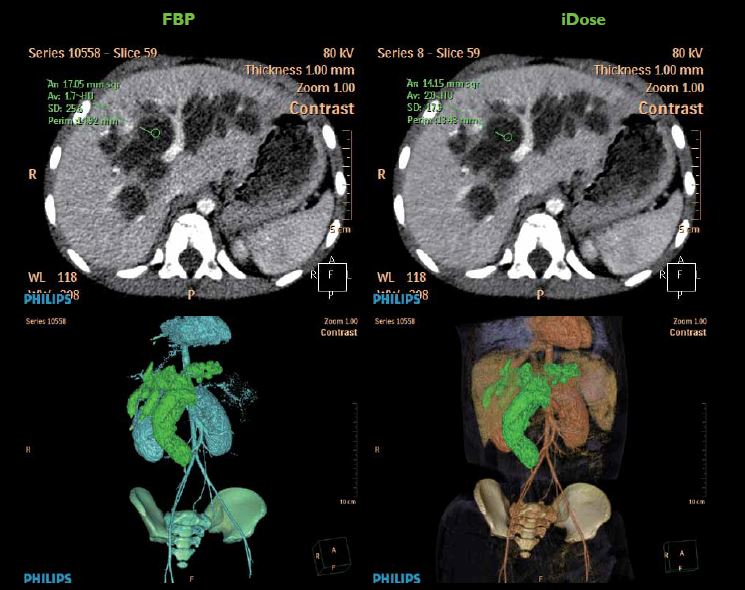

绿色高清

市场是最优秀的低剂量迭代平台iDose4,给您低剂量高清成像,保证了病人的健康诊疗。